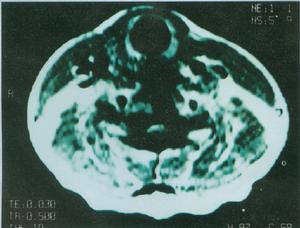

遺傳性痙攣性截癱HSP的診斷主要基於臨床症狀體徵,陽性家族史,並排除其他疾病。因此,HSP的鑑別診斷很重要,特別是對臨床特徵不典型及沒有相同疾病家族史的患者。目前,基因診斷已成為可能,但只限於已克隆的5型疾病基因的突變檢測。肌活檢有助於HSP-7型的診斷頸椎病常有上肢受累,神經根性疼痛,頸椎X線片及MRI示頸椎骨質增生。多發性硬化有緩解與復發的病史,視神經炎,MRI示腦部脫髓鞘改變。肌萎縮側索硬化有上肢肌萎縮,肌束震顫,肌電圖示巨大電位改變。Arnold-chiari畸形有共濟失調錶現,頭顱MRI可確診。脊髓小腦型共濟失調以共濟失調錶現為主,眼球運動障礙,構音障礙等。本病須與Arnold-Chiari畸形、頸椎病,多發性硬化、腦性癱瘓和遺傳運動神經元病等鑑別。

3、MRI頭顱MRI一般無異常,但某些病例可表現胼胝體發育不良,大腦、小腦萎縮。頸段或胸段脊髓MRI可顯示脊髓萎縮。